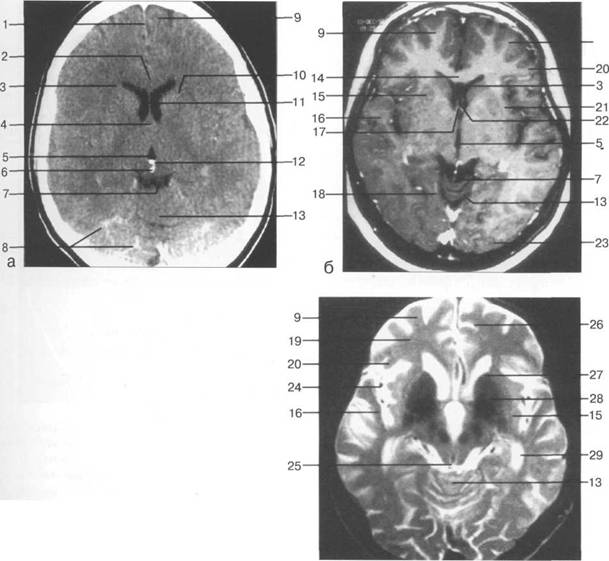

височная доля; 17 - полушарие мозжечка; 18 - |

цистерна четверохолмия; 14 -прямой синус; 15 -лобный рог; 16 - головка хвостатого ядра; 17 -перед